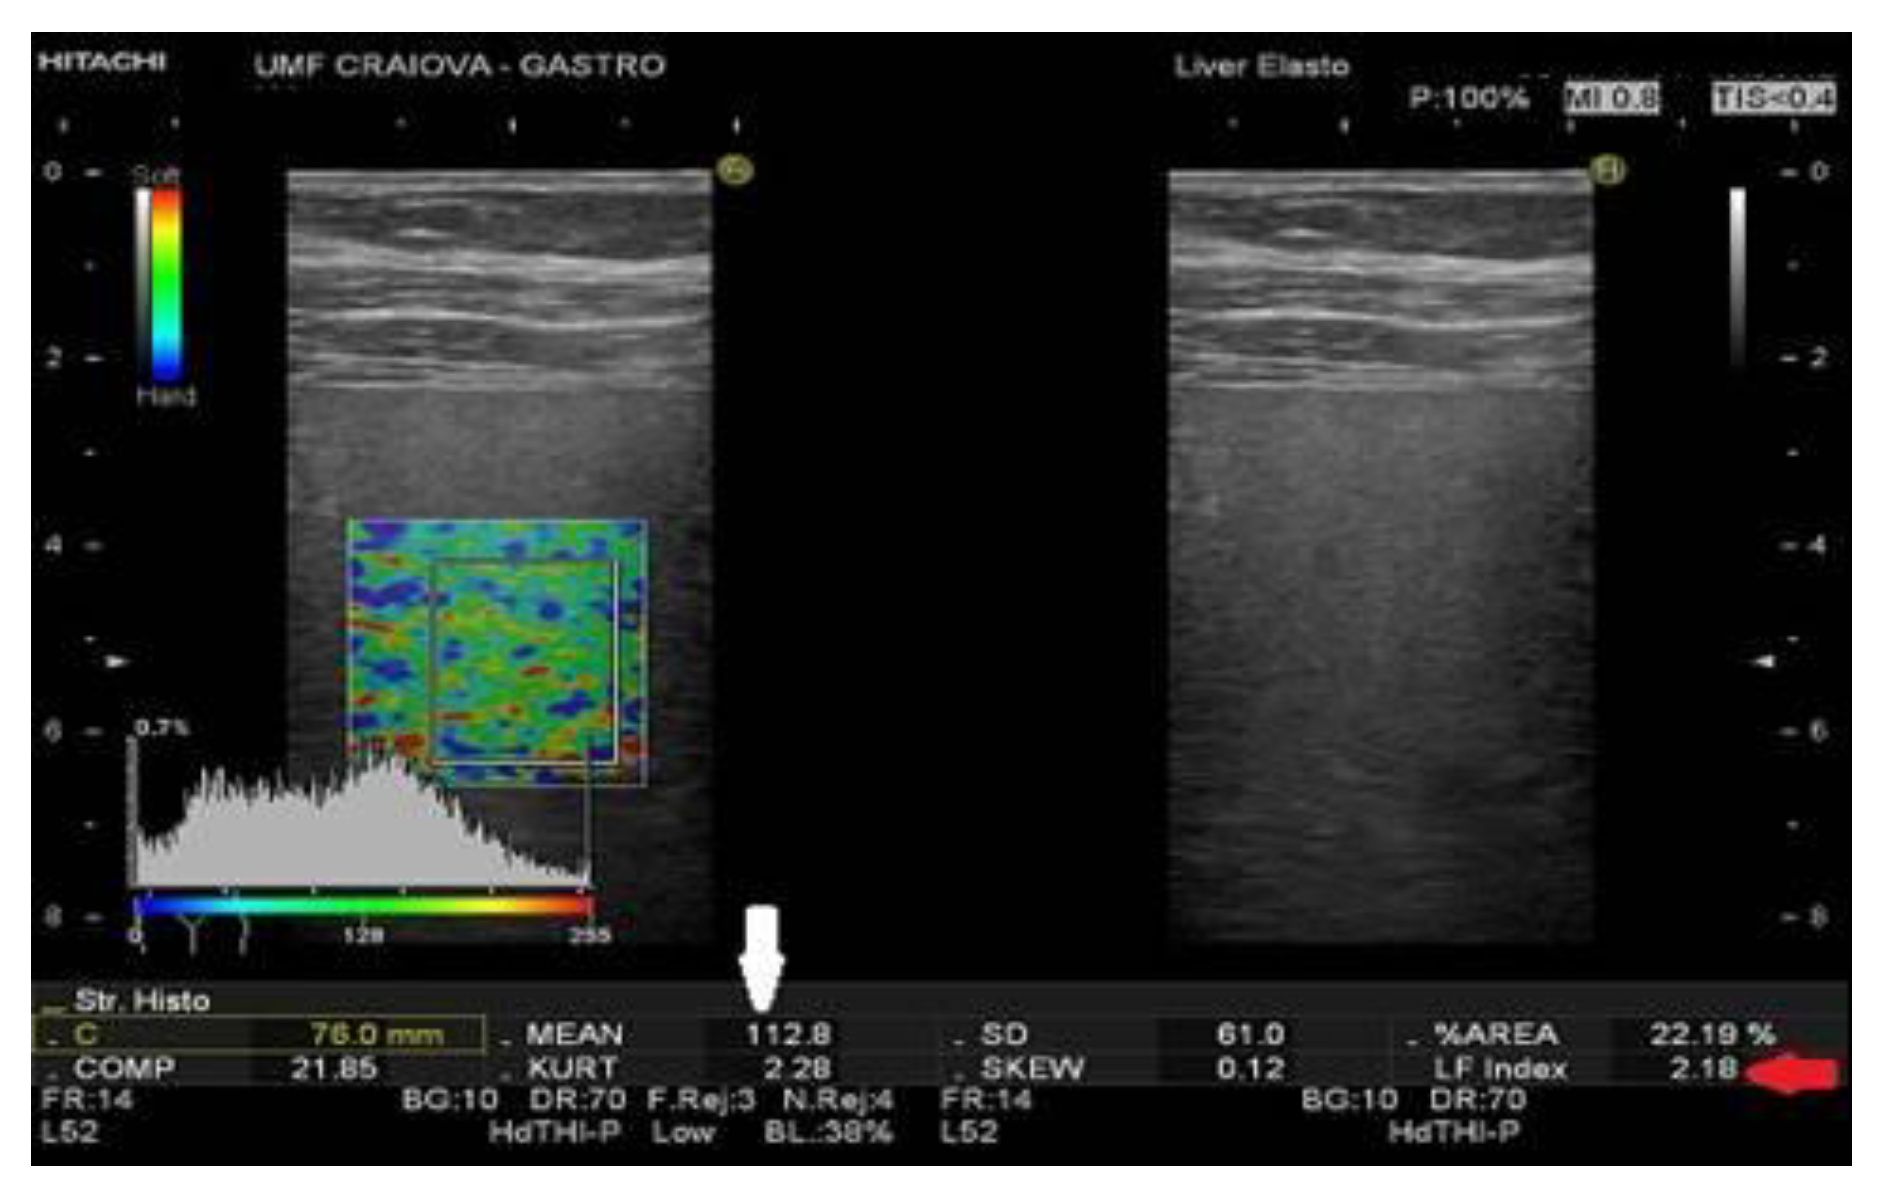

For a better evaluation of the hepatic status, a real time sonoelastography (RTE) was carried out, that emphasized a tessellated structure with the predominance of the blue areas and a liver fibrosis index (LFI) of 2.18.

Figure 2. RTE reveals the predominance of the blue areas and a LFI of 2.18.

In our case, the patient is a C virus carrier, with active replication for several years, being subjected to several investigations for the evaluation of hepatic function. The prognosis of the hepatic disease is based on the degree of fibrosis, a proper, complete, and early evaluation being essential. Although the hepatic biopsy remains the “gold standard,” a series of noninvasive techniques concerned with the evaluation of the degree of fibrosis, including RTE, have recently been recently. This contemporary and noninvasive method enables evaluation of the differences of hardness between affected and healthy tissues, with applicability that varies from the differentiation of malign tumors from benign ones via the evaluation of the degree of elasticity specific to a tumoral tissue, up to the evaluation of the degree of hepatic fibrosis [36].

The status of being a non-responder exposed the patient to both the progressive deterioration of the hepatic function, with the gradual installation of cirrhosis and its complications, and the development of a hepatocellular carcinoma, which led to the use of periodical RTE, as this technique can be applied in either case. By the LFI, the degree of hepatic fibrosis and potential tumorous formations can be determined.